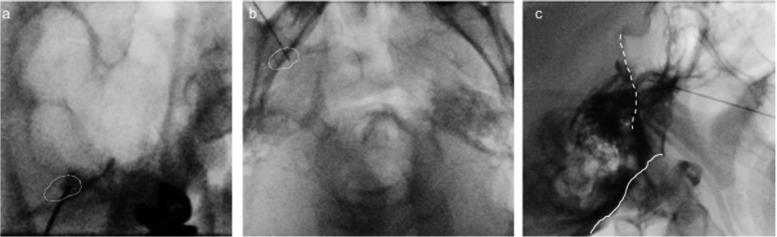

A 49-year-old male with multiple sclerosis exhibited persistent dull pain and paroxysmal electric shock-like pain in his bilateral maxillary molars and mandible. He was diagnosed with trigeminal neuralgia due to multiple sclerosis. Due to severe side effects, it was difficult to achieve adequate pain control with medication alone. By performing low-temperature radiofrequency thermocoagulation and pulsed radiofrequency of the Gasserian ganglion while monitoring masseter muscle contraction, a satisfactory and rapid analgesic effect was obtained without masticatory atonia.

一名49岁的多发性硬化男性患者双侧上颌磨牙和下颌出现持续性钝痛和阵发性电击样疼痛。他被诊断为继发于多发性硬化的三叉神经痛。由于严重的副作用,仅靠药物难以实现充分的疼痛控制。通过在监测咬肌收缩的同时对半月神经节进行低温射频热凝和脉冲射频治疗,获得了满意且快速的镇痛效果,且未出现咀嚼肌麻痹。